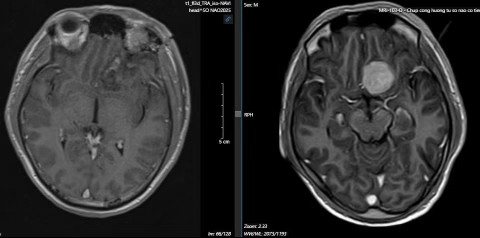

Trong tuần qua, Bệnh viện Việt Đức đã thực hiện thành công hai ca phẫu thuật cắt u màng não ở tầng trước nền sọ bằng kỹ thuật này. Cả hai bệnh nhân đều có khối u nằm ngay trên trần hố mắt. Một bệnh nhân có khối u đường kính 1,8cm và một bệnh nhân có khối u gần 3cm. Cả hai ca phẫu thuật đều thành công, bệnh nhân phục hồi tốt.

| Phim chụp MRI trước mổ (bên phải) và sau mổ (bên trái) cho bệnh nhân. |